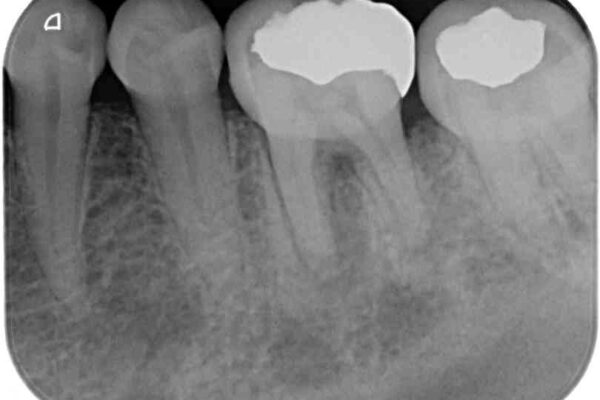

以前むし歯治療をした後から定期的に痛むことがあるとのことで、レントゲン写真より神経組織が失活していることが予想されました。

術後6ヶ月でレントゲン写真を撮影したところ、出血の原因であった穴付近の溶けていた骨が回復している様子が認められました。